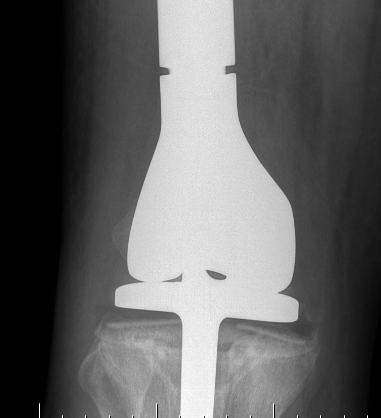

Post proximal tibial osteosarcoma resection

- modular endoprosthesis for osteosarcoma of the proximal tibia

- 55 patients

- 5 year prosthesis survival 82%

- 10 year prosthesis survival 62%

- aseptic loosening commonest complication 14.5%

- deep infection 14.5%

- periprosthetic fractures 16%